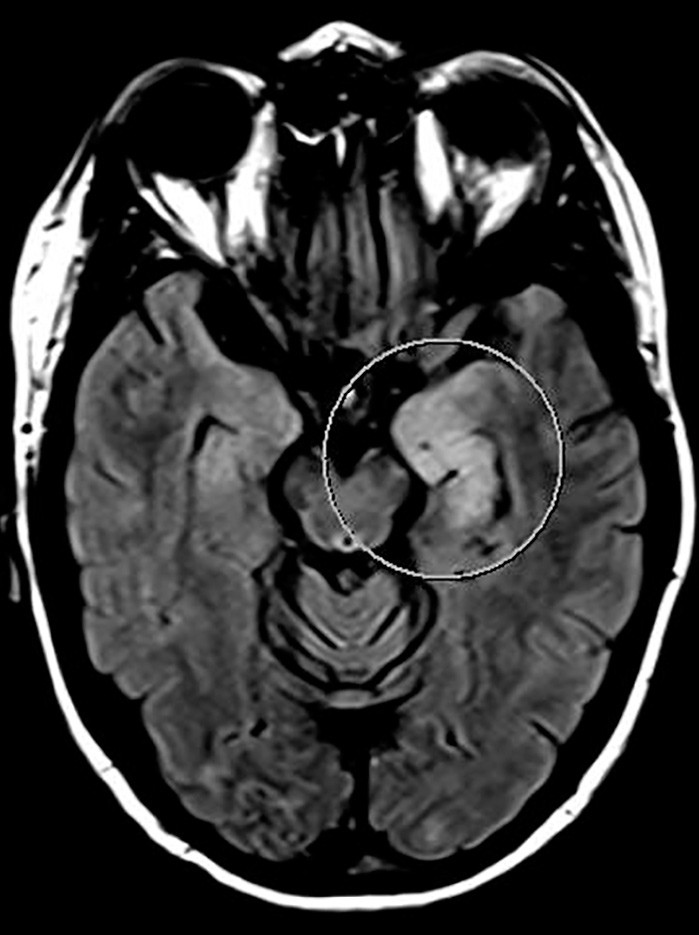

I løpet av et par dager ble pasienten somnolent og fikk økende muskeltonus i alle fire ekstremiteter, økte reflekser og bilateral plantarinversjon. CRP steg til 130 mg/l (< 5 mg/l), leukocytter til 18 · 10⁶/l (4,5 · 10⁶/l) og SR til over 100 mm/h. Gjentatte spinalpunksjoner viste lett leukocytose (16 · 10⁶/l celler) og lett forhøyet totalprotein (0,66 mg/l). Isoelektrisk fokusering av spinalvæske var uten tegn til intratekal IgG-produksjon. EEG endret seg på seks dager fra nærmest normalt til svært patologisk, med generalisert høyspent, langsom theta- og deltaaktivitet samt hyppige, skarpe potensialer frontotemporalt med trifasisk utseende. MR caput viste progresjon av signalavvikene i mediale venstre temporallapp (amygdala, uncus og fremre hippocampus) i basalgangliene og subkortikalt i begge hemisfærer (fig 2a og b).

Signalforandringene i disse områdene var uten tegn til diffusjonsrestriksjon, noe som talte mot ferskt iskemisk infarkt. MR-bildene ga derimot mistanke om viral encefalitt eller limbisk encefalitt. Det var imidlertid ikke påvist affeksjon av insula, basale frontallapp og gyrus cinguli, som ofte er involvert ved limbiske encefalitter (6).

Pasientens tilstand ble ytterligere forverret. Hun reagerte ikke på smertestimulus eller tilrop, ble spastisk i alle ekstremiteter, nakkestiv og hadde bilateral plantarinversjon. MR caput viste ytterligere progresjon av høysignalområder i begge hemisfærer, både i basalganglier, subkortikalt og kortikalt (fig 3). På grunn av manglende respons på steroider og immunoglobuliner samt rask og betydelig klinisk forverring, valgte vi å starte med immunsuppressiv behandling i form av rituximab 1 000 mg intravenøst.